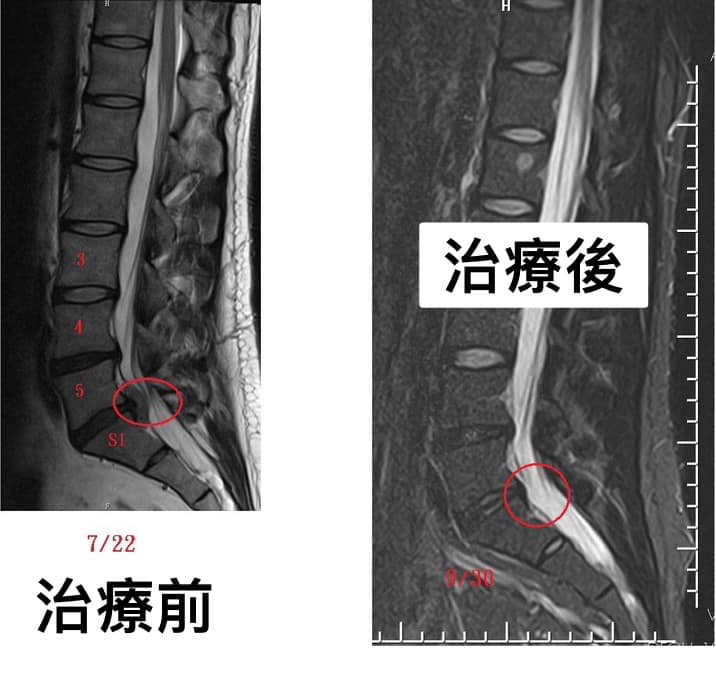

⭕️七週治療椎間盤明顯吸收回去。

感想:每一次看到患者症狀改善很多當然開心,更興奮的是突出的骨刺在術後的核磁共振也發現有吸收的現象!皆大歡喜啊。

⭕️脊椎整合中醫微創療法可在關節面跟惻隱窩減壓,讓椎間盤內的高壓下降,搭配針灸刺激多裂肌與核心肌群的增生,讓脊上韌帶恢復力量,對抗椎間盤突出,自然提供一個很好髓核自行吸收的環境。